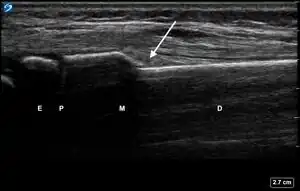

| 2 | Obtain, label, and save an image of the epiphysis (E), physis (P), metaphysis (M), and diaphysis (D). | ![]() | |